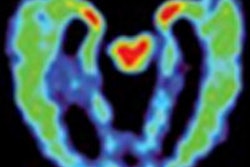

PET/CT images show a Hodgkin's lymphoma patient with a negative PET scan after chemotherapy. There is high uptake in lymph nodes on both sides of the neck prior to treatment (above), which resolved after chemotherapy (below). Physiological uptake is also seen in the heart and bladder. Images courtesy of Dr. Sally Barrington, reader in nuclear medicine, PET Imaging Centre at St Thomas' Hospital in London.Hodgkin's lymphoma occurrence

PET/CT images show a Hodgkin's lymphoma patient with inadequate response to treatment or "positive" PET scan after chemotherapy treatment. There was high uptake in lymph nodes on both sides of the neck prior to treatment (above) with persistent high uptake in the right neck after treatment; Deauville score 5 (below). The Deauville criteria is a five-point scoring system used to calculate uptake in PET images. A score of 5 would indicate the greatest amount of uptake. Physiological uptake is seen in the bladder.Follow-up research